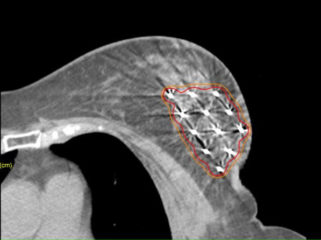

La Braquiterapia también se aplica en casos particulares de pequeños tumores y de mujeres menopáusicas. Después de haber sido sometidas a una mínima cirugía se les trata solamente una parte de la mama con Braquiterapia de Alta Tasa y en 5 días concluyen en tratamiento. Un tratamiento en el que el Hospital Nisa Virgen del Consuelo tiene ya experiencia y que es reconocido como efectivo por Sociedades Internacionales como tratamiento de elección.